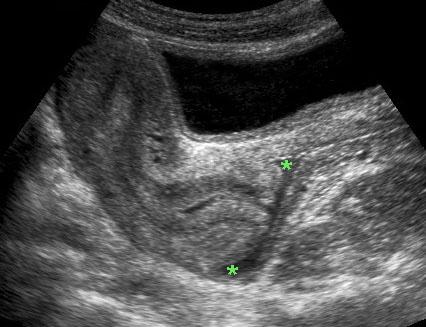

Mặt cắt dọc của tử cung bình thường với một ít dịch trong lòng âm đạo, giúp xác định rõ phần âm đạo của cổ tử cung (portio) cũng như túi cùng trước (*) và túi cùng sau (*).

Một ít dịch trong túi cùng Douglas và một nang Naboth nhỏ (n.) có thể dễ dàng nhận biết, nhưng các cấu trúc được đánh dấu bằng dấu chấm hỏi là gì?